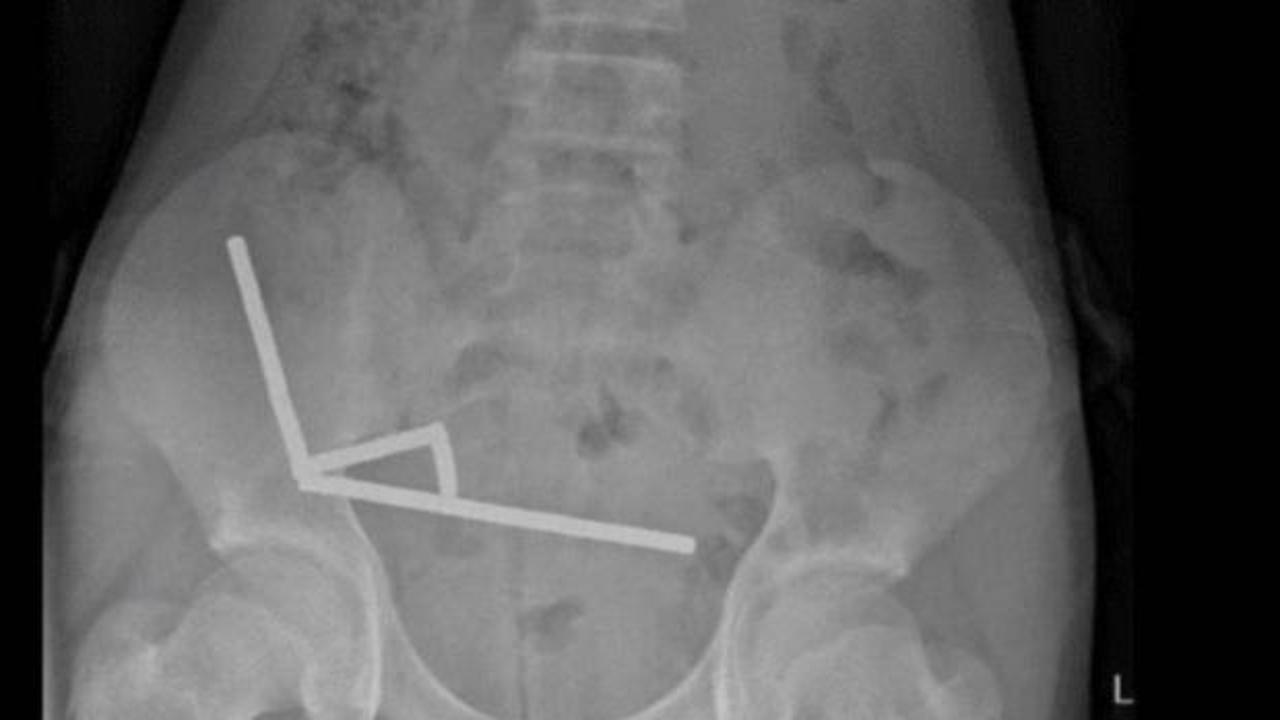

Röntgen görüntülerinde, çocuğun bağırsağında dört ayrı bölgede zincir halinde dizilmiş metal toplar görüldü. Ameliyatta bu zincirlerin ince bağırsak ve çekumda (kalın bağırsağın başlangıcı) birbirine yapışarak dokularda kan akışını engellediği ve “basınç nekrozu” denilen doku ölümüne yol açtığı tespit edildi.